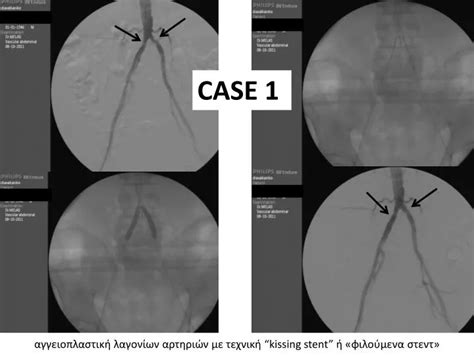

Alright, let’s get down to the nitty-gritty of the kissing stent procedure . Think of it like this: instead of placing just one stent, doctors strategically place two stents in a way that they ‘kiss’ or touch each other at the bifurcation point. The main idea is to support both the main vessel and the important side branch, ensuring that neither gets squashed or blocked by the stent. Usually, one stent is placed in the main artery, and the second stent is placed in the side branch. The ‘kissing’ part comes from the technique used to position and deploy these stents. After the initial placement, a balloon catheter is often used to gently expand both stents simultaneously or sequentially, making sure they conform perfectly to the vessel walls and create a smooth channel for blood flow. This technique is particularly useful when the blockage is significant and involves the ostium, which is the opening, of the side branch. Without this specialized approach, treating such a lesion could lead to restenosis (re-narrowing) or stent thrombosis (blood clot formation within the stent) in the side branch. The kissing stent procedure aims to mitigate these risks by providing comprehensive coverage and support to the critical bifurcation area. It’s a testament to the ongoing innovation in interventional cardiology, constantly seeking better ways to tackle complex cardiovascular challenges and improve patient outcomes. The precision involved is remarkable, requiring a skilled hand and a deep understanding of vascular anatomy.

So, what can you expect if you’re going in for a kissing stent procedure ? Don’t worry, it’s generally a minimally invasive process. First off, you’ll likely be given some medication to prevent blood clots and keep you comfortable. The procedure is typically performed while you’re awake, but you’ll receive sedatives to help you relax. The access point is usually in your groin or wrist, where a small incision is made. A thin, flexible tube called a catheter is then guided through your blood vessels, all the way to the blocked area in your heart. Real-time X-ray imaging (fluoroscopy) is used to guide the catheter precisely. Once the catheter is in place at the bifurcation, the interventional cardiologist will deploy tiny balloons to confirm the blockage and prepare the area. Then, the kissing stent procedure really begins. Two stents, mounted on balloon catheters, are carefully positioned. One stent goes into the main artery, and the other goes into the side branch. The balloons are inflated, expanding the stents against the artery walls, and then withdrawn. Sometimes, a final inflation of a balloon is done across both stents to ensure they are well-apposed and open. The whole process usually takes a couple of hours. It’s a highly skilled procedure, focusing on restoring optimal blood flow to both the main vessel and the crucial side branch. The minimal invasiveness means a quicker recovery compared to open-heart surgery. Your medical team will be monitoring you closely throughout, ensuring your safety and comfort every step of the way. They’ll explain everything as it happens, so you’re always in the loop.